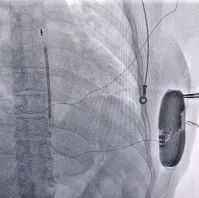

心律失常中心高连君主任及尹晓盟主任亲自制定手术方案并指导手术,由于晓红教授和孙伟医生主刀,手术在全身麻醉下进行,因患者为年轻女性,平素体力活动大,为避免电极导线移位,手术采用三切口方式,通过隧道穿引针将除颤电极从囊袋经隧道送至剑突下切口,固定电极中段,再将电极经隧道送至胸骨上方切口,固定头端。连接脉冲发生器A209,置入囊袋内,逐层缝合关闭囊袋,进行DFT测试,采用50HZ,200MA交流电方式进行诱颤,S-ICD正确识别,经首次65J除颤成功,除颤阻抗67欧姆。手术圆满成功,耗时不到1小时。

此次手术,为患者选用了可进行1.5T核磁全身扫描的A209除颤器和3501除颤导线这一全新组合,该组合也是兼容MRI全皮下植入式心律转复除颤器的国内首批植入。